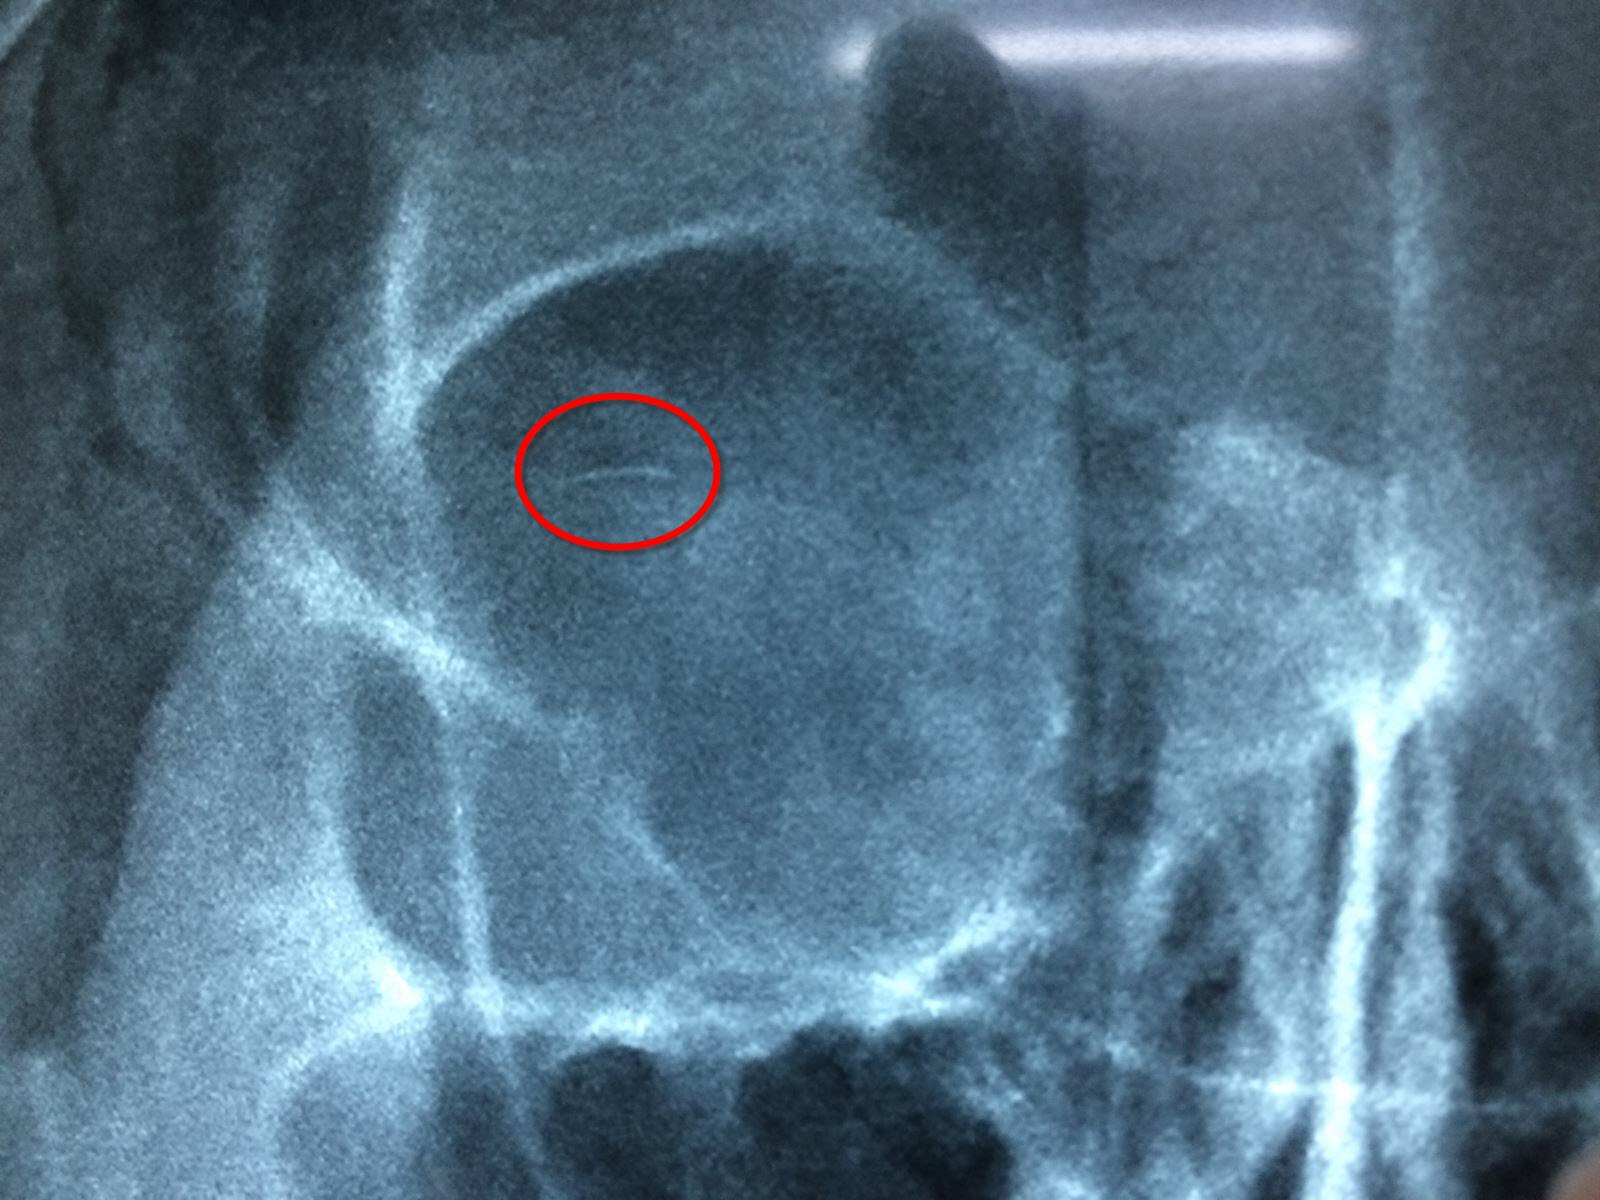

BN Vũ Thị L.24 tuổi khá xinh nhưng vẫn muốn xinh hơn vào khoa Chấn thương ngày 23/4/2018 vì đang tạo hình mí ở cơ sở làm đẹp thì bị mất kim, tua trực mặc dù đã phẫu thuật ngay nhưng vẫn không tìm được kim. Phim X- quang phải quan sát kỹ lắm mới thấy được lờ mờ  cây kim dài khoảng 5mm, đường kính khoảng 0,2 mm to đúng bằng chiếc lông mi nằm ở 1/3 trên ngoài hốc mắt, song song với cùng đồ kết mạc. Kim thường dẻo, di động tốt có thể làm sát thương cho nhãn cầu, chế bằng hợp kim nên bắt nam châm rất kém, đã mổ một lần…làm tôi ngao ngán. Tua lại trong đầu những hình ảnh và clip kỹ thuật khâu chìm, không có đường rạch của xu hướng tạo nếp mí phổ biến ở các nước châu Á…Tôi dự đoán kim thường bị mắc lại ở 1/3 trên sụn hay trong khoang giữa kết mạc, sụn và cơ Muller- vốn rất chật hẹp. Mở lại đường mổ cũ, máu đã khô, thám sát bằng tay- mắt không thấy kim đâu. Miết khẽ ở bờ trên sụn và túi cùng kết mạc mi trên chỉ thấy hơn lợn gợn ở 1/3 ngoài. Dùng chỉ mi và vành mi đơn để nhìn rõ toàn bộ cùng đồ kết mạc, kíp mổ mừng rơn khi nhìn thấy cây kim lấp ló. Lấy kim, chụp ảnh và đóng lại vết mổ cũ thôi! Chúng tôi đã có thêm kinh nghiệm quí báu để xử lý những tai biến loại này.